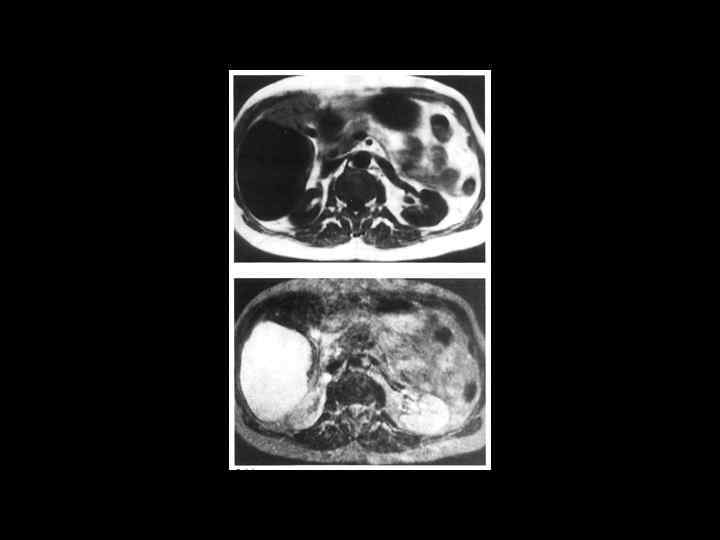

Тот же пациент

АКТУАЛЬНЫЕ ВОПРОСЫ РЕНТГЕНОЛОГИИ ЛУЧЕВАЯ ДИАГНОСТИКА ОЧАГОВЫХ ПОРАЖЕНИЙ ПЕЧЕНИ МЕТАСТАТИЧЕСКОЕ ПОРАЖЕНИЕ ПЕЧЕНИ МР семиотика: Т 1 взвешенные изображения - множественные участки со слабым сигналом Т 2 взвешенные изображения - яркий сигнал от метастазов